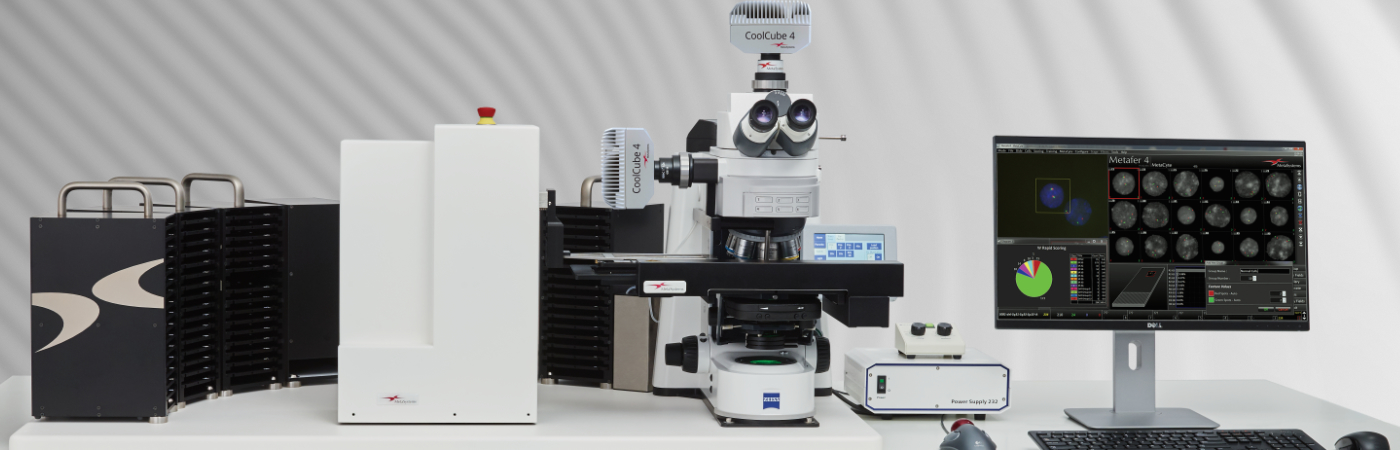

Metafer is a software platform designed to manage standard microscopes and related hardware. It facilitates the scanning of light microscope slides, the acquisition of digital images, the application of standard image processing techniques, and the measurement of general image features.

Utilizing the Metafer software, imaging systems scan specimens of diverse sizes, employ various contrasting methods and magnifications, and identify, classify, and enumerate cells or other objects. Metafer's modularity and flexible architecture make it proficient in assisting users from various fields with their specific imaging tasks.

The flexible smart scanning facilitated by Metafer software suggests numerous options, each tailored to specific hardware accessories and software requirements, for various customizations. A variety of software license subsets and hardware options are at your disposal. Commonly, Metafer software-controlled integrated systems consist of one of four camera models and a motorized stage. A fully integrated system requires a motorized microscope. MetaSystems can incorporate the microscope into the installation, although the Metafer software can also be integrated with existing, compatible microscopes.

Please note that the hardware components depicted are not part of the Metafer IVD product and are supplied by third-party manufacturers.